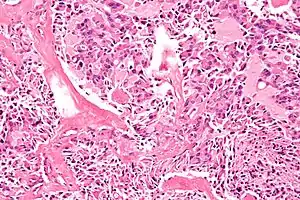

Micrograph of a medullary thyroid carcinoma, as may be seen in MEN 2A and MEN 2B. H&E stain